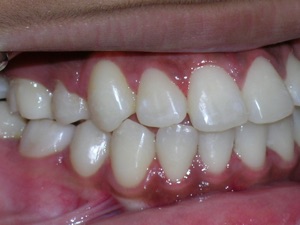

Here’s a young lady who presented with severe crowding. Often we think of crooked teeth as being limited to front teeth. Here one can see that back teeth can also get crowded. Braces were placed and select teeth were removed. Watch.

Here again we used a “Nance” holding arch. Look at some photos while the braces are on.